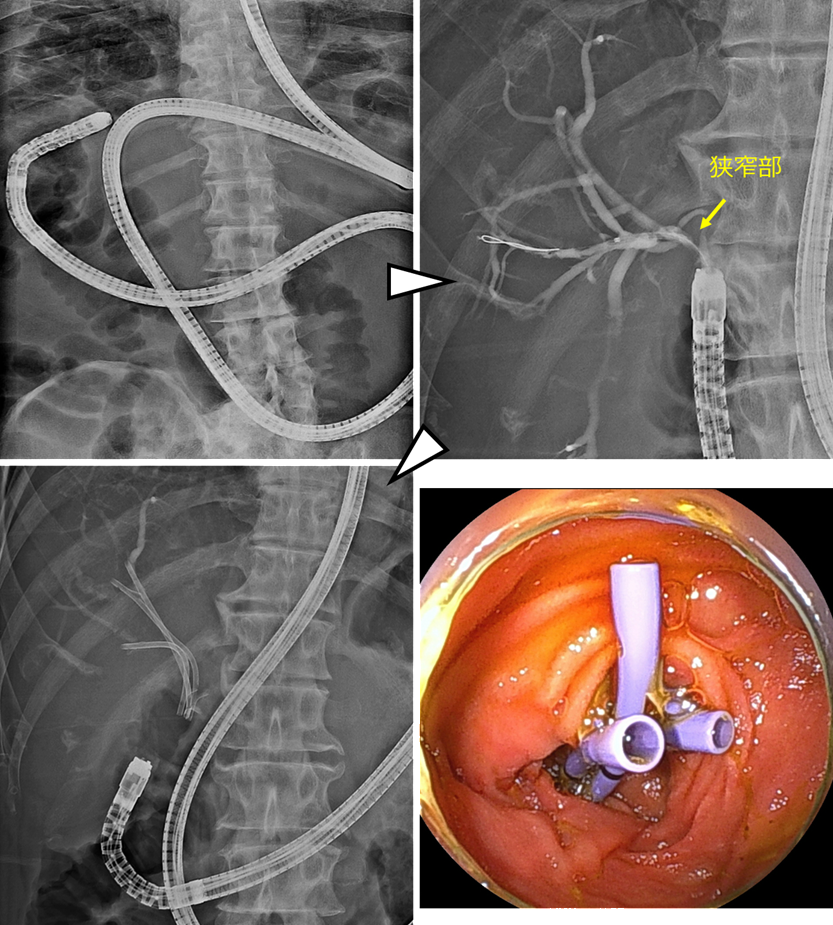

左上:Roux-en-Y再建後でした。ダブルバルーン内視鏡を用いました。

右上:到達後、胆管造影を行い、狭窄部の確認をしました。

左下・右下:前区域枝に2本・後区域枝に1本のステントを留置しました。

本症例はRoux-en-Y再建後であり、ダブルバルーン内視鏡を用いて胆管まで到達しました。胆管造影を行い、狭窄部を確認した後、前区域枝に2本、後区域枝に1本、合計3本のステントを留置しました。